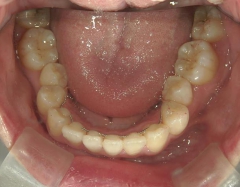

矯正_灰色.pngno.8_8495_治療前_下.jpg矯正_灰色.png

矯正_灰色.pngno.8_8495_治療後_下.jpg矯正_灰色.png